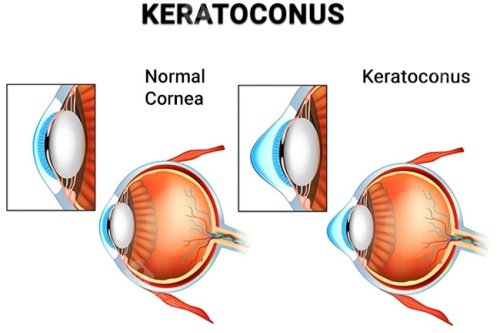

圆锥角膜交联手术哪家强?爱尔眼科、普瑞眼科、华厦眼科、朝聚眼科、新视界眼科都是做圆锥角膜交联手术口碑好的正规眼科医院!

早期圆锥角膜:单用交联术稳定角膜形态